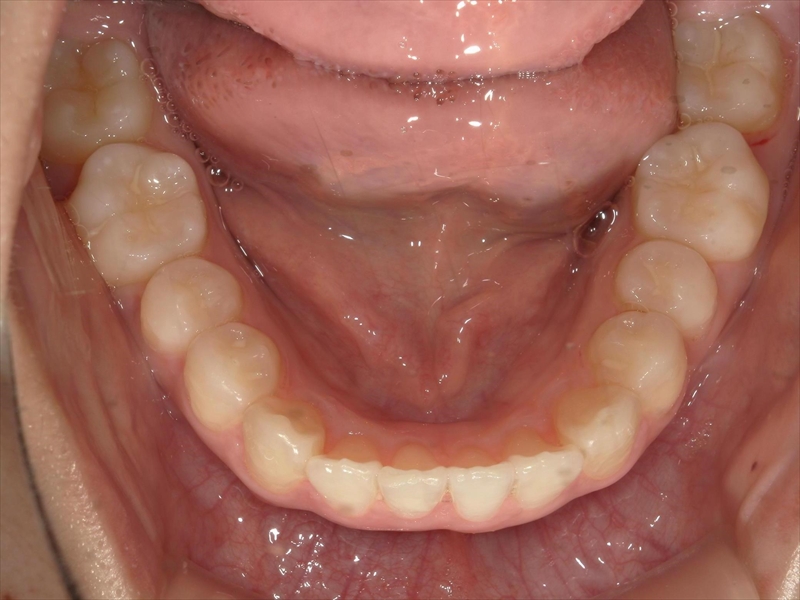

この患者様は、重度の出っ歯があり、下顎前歯には叢生が認められました。

下顎の治療計画について

- 上顎出っ歯が原因で下顎前歯が上に伸び過ぎているため、圧下

- 犬歯から小臼歯までが捻じれていたため、正しい位置へ

- 大臼歯は内側へ入れ

- これらのスペースを確保するため、歯を削る(IPR)